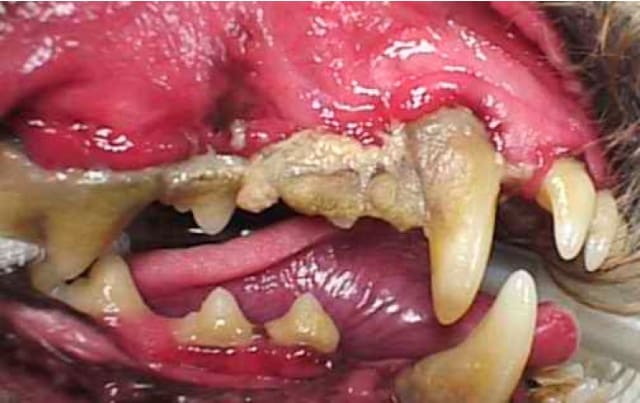

Stage 4 – SEVERE

Teeth have advanced breakdown of support tissues with severe pocket depth.  Signs include severe calculus accumulation, dead tissue with blood and pus, severe halitosis, significant bone loss, and mobility of teeth. Patients require tooth extractions and oral surgery.